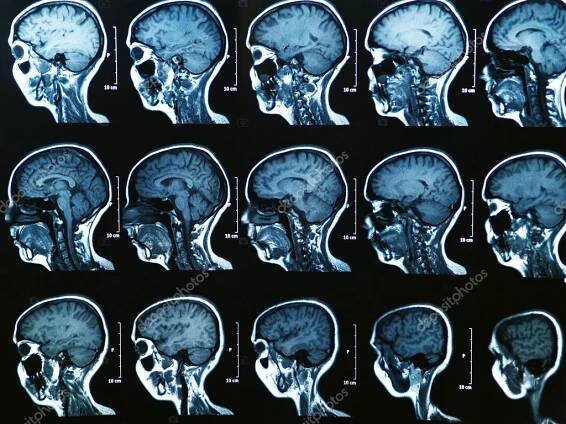

Mri Sken Mozku Axiální Sagitální Pohled Referenční Linií Pro Detekci ...

Magnetická rezonance (též MR, MRI, z anglického „magnetic resonance imaging“) je zobrazovací technika používaná především ve zdravotnictví k zobrazení vnitřních orgánů lidského těla.

Magnetické rezonanční zobrazování (také označovaná jako MRI - zkratka z Magnetic Resonance Imaging) je test, který využívá silné magnety, rádiové vlny a počítač pro vytváření detailních snímků uvnitř těla.